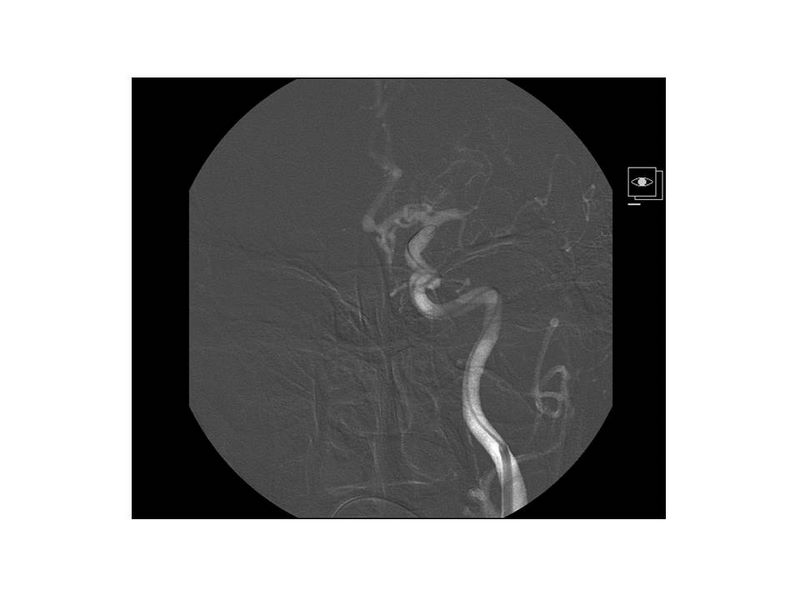

Ictus con stent